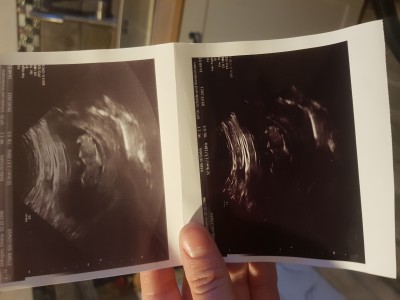

Merabalar kızlar nub teorisi diye bir şey varmı orda cinsiyetle ilgili bana da fotograflarıma bakarak cinsiyet tahmini yaparmısınız

Gebelik haftası 20

Nub teorisi neymiş bilmiyordum baktım da sizinki erkek o zaman :) kesin birşey değildir heralde bu ya çok da anlamam kendi bebeğimin de cinsiyetini bilmiyorum doktor kıza benziyor dedi nub teorisine göre bakınca da kız o zaman benimki :):)